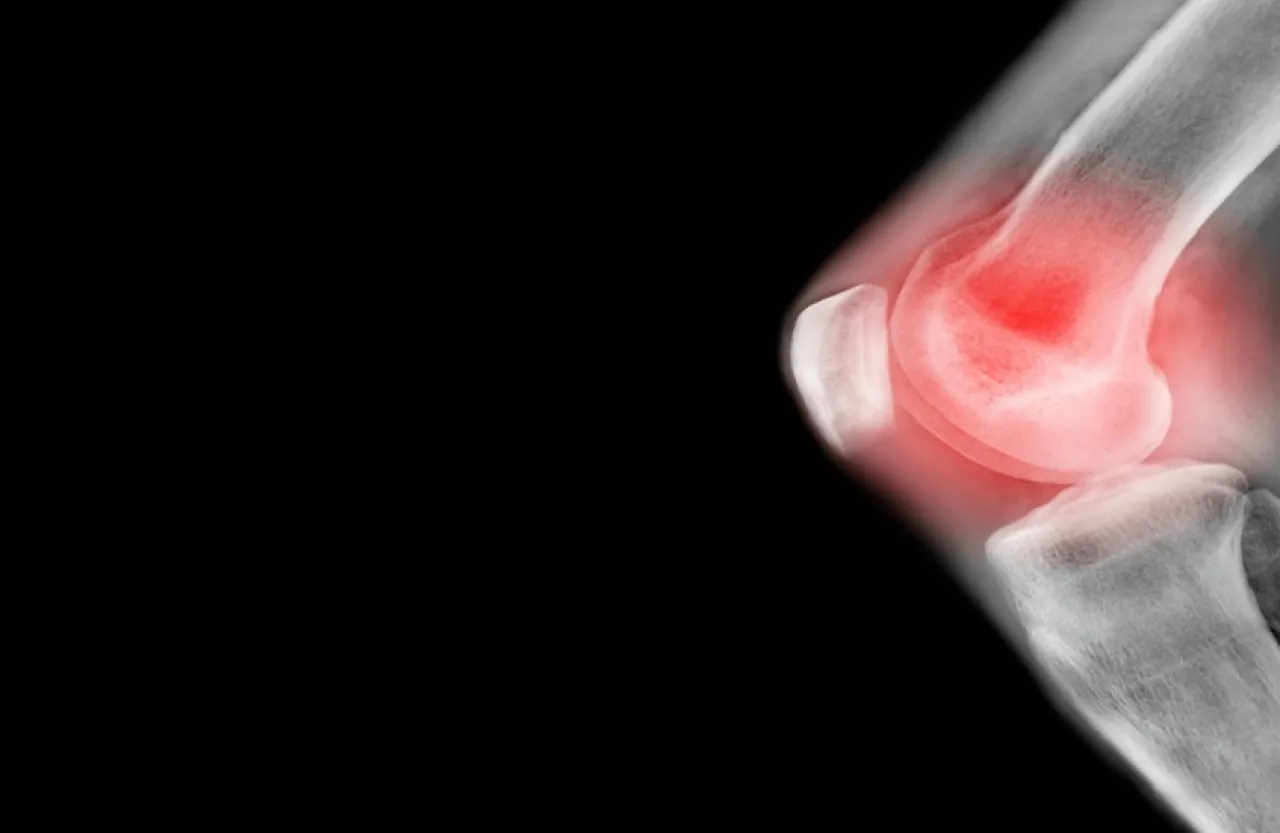

خبرني - أظهرت دراسة أجراها باحثون أستراليون أن تمارين اليوغا لها أثر فعال في علاج آلام مفاصل الركبة.

وشملت الدراسة 117 شخصا أعمارهم تبدأ من 40 عاما، تم تشخيص إصابتهم بهشاشة العظام ويعانون من آلام في مفصل الركبة، وتم تقسيم المشاركين إلى مجموعتين: مجموعة طلب منها ممارسة تمارين القوة لاختبار فعالية هذه التمارين على تخفيف آلام مفاصلهم، والأخرى طلب منها ممارسة تمارين اليوغا.